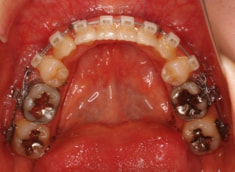

治療前

治療開始時

修復歯、補綴歯もあります。下顎8番が水平埋伏しています。